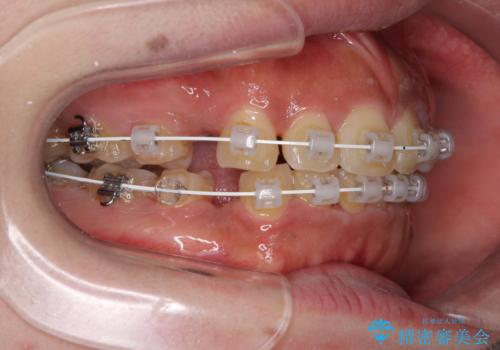

- 審美装置

- 1年11ヶ月

- 10-30回

口腔内の清掃性に問題があり、虫歯のリスクが極めて高かったため、短期で治療を終えることを最優先に治療を進めました。